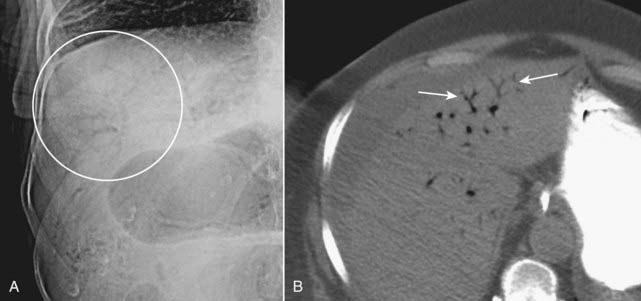

image

Figure 15-11 Pneumatosis seen in profile.

Close-up of the right lower quadrant in an infant demonstrates a thin curvilinear lucency that parallels the lumen of the adjacent bowel (solid white arrows), an appearance characteristic of gas in the bowel wall seen in profile. In infants, the most common cause for this finding is necrotizing enterocolitis, a disease found mostly in premature infants in which the terminal ileum is most affected. Pneumatosis intestinalis is pathognomonic for necrotizing enterocolitis in infants.

Figure 15-12 Pneumatosis seen en face.

Close-up of the right lower quadrant in another infant shows multiple faint, mottled lucencies in the right lower quadrant (white circle), which is the appearance of pneumatosis intestinalis when seen en face. The density has the same appearance as air mixed with stool, but can be distinguished from stool because it occurs in areas stool might not be expected and it does not change over time. This infant also had necrotizing enterocolitis.